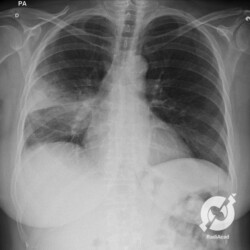

E o nome dado a esta alteração radiográfica que corresponde à substituição do ar alveolar por líquido é a consolidação alveolar.

Uma consolidação alveolar é, por definição, uma opacidade (imagem densa, branquinha) homogênea ou às vezes heterogênea (pela presença de calcificações ou cavidades), de limites mal definidos, exceto quando toca a pleura da parede ou das cissuras pulmonares. É um termo usado tanto em radiografia, como em tomografia computadorizada. Na tomografia, um outro termo é usado: vidro fosco, que é uma opacidade (branquinha mas não tanto como a consolidação), que borra o pulmão mas deixa ver os vasos de permeio (igual bigode de adolescente: dá pra ver todo o fundo).

Nós vamos mostrar aqui um pequeno apanhado de pneumonias de variados agentes, em diversos segmentos e lobos pulmonares, com extensões variadas. O objetivo é identificar o padrão radiológico de consolidação alveolar e não determinar o agente infeccioso, isso vai ser assunto para mais adiante. Aliás já antecipo que é fundamental saber localizar a lesão, porque alguns destes bichos gostam de determinados segmentos, alguns tumores também têm as suas preferências, então localização é fundamental. Se localização não fosse importante, um apartamento na beira do mar sairia o mesmo preço de um apartamento de frente pra BR-101, concordam?

Seguem alguns dos nossos casos de pneumonia para vocês treinarem os olhos e não se apavorarem nos plantões.